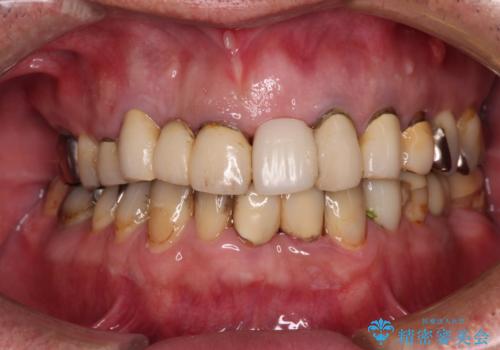

転倒で折れてしまった前歯 インプラントによるオールセラミックブリッジ治療

- 転倒により前歯3本が折れてしまったとのことで、インプラントによる治療を希望して来院された患者様です。

既に近医で真ん中の歯1本は抜歯されており、その隣の2本も破折していると言われたとのことでした。

診断をした結果、前医の診断の通り、2本とも破折しており、既に抜去している歯を含めて3本の抜歯が必要な状態でした。

抜歯する歯の両隣も治療が必要と思える歯であったため、広範囲なオールセラミックブリッジによる治療も提案しましたが、患者様本人の希望もあってインプラント2本による欠損部のみのブリッジ治療を行うこととしました。

歯の破折による抜歯のため、歯槽骨の欠損が大きく、骨造成処置の併用が必要であり、骨造成が落ち着くまでに半年ほど時間を要することになります。

2本同時に抜去して一時的な入れ歯の使用を提案しましたが、極力固定式の仮歯を使用したいとのことで、半年に1本ずつ埋入することとし、トータルで1年強を要する治療計画となりました。

治療により前歯は非常に安定しましたが、インプラント部の両隣、特に反対側の前歯はクラウンのやり直しが必要な状態であったので、今後反対側の治療も実施していく予定です。